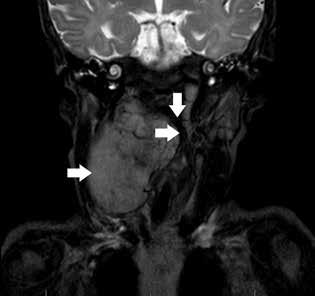

Flexible fiberoptic laryngoscopy revealed a bulging right lateral pharyngeal wall and a normal epiglottis, supraglottis, and vocal folds. Magnetic resonance imaging (MRI) confirmed a pharyngeal mass from C1 to C7 measuring 1.6 × 5.1 × 6.4 cm with heterogeneous enhancement and a mass effect with displacement of the oropharyngeal airway (figure 1). The MRI also revealed an enlarged level II right cervical lymph node measuring 12.5 × 8.5 × 3.0 mm. The differential diagnosis included neuroblastoma, rhabdomyosarcoma and, less likely, neurofibroma.

From the Department of Otolaryngology (Dr. Shields and Dr. Mitchell), the Division of Pediatric Hematology–Oncology, Children’s Medical Center (Dr. Lampson), and the Department of Pathology (Dr. Sengupta), University of Texas Southwestern Medical Center, Dallas. Figure 1. Coronal section of T2-weighted MRI reveals a large, hyperintense pharyngeal mass compressing the airway.